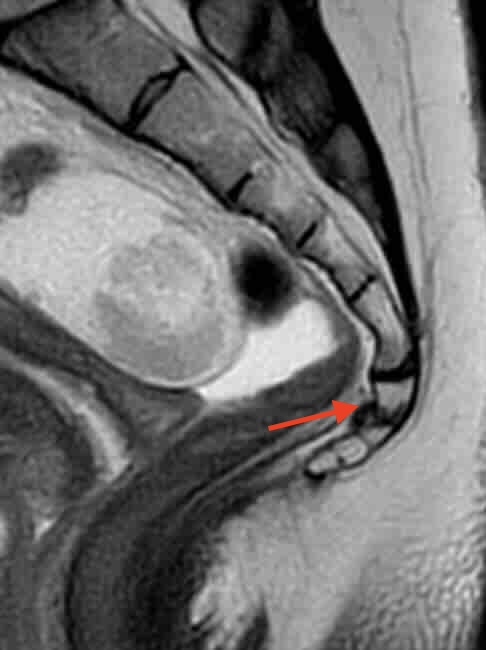

También es necesaria una resonancia magnética de sacro-coxis para valorar el estado óseo, de ligamentos y partes blandas. Es necesario descartar enfermedades como tumores rectales, problemas ginecológicos o urológicos.

Resonancia magnética señalando con una flecha roja la ubicación exacta de una fractura de coxis